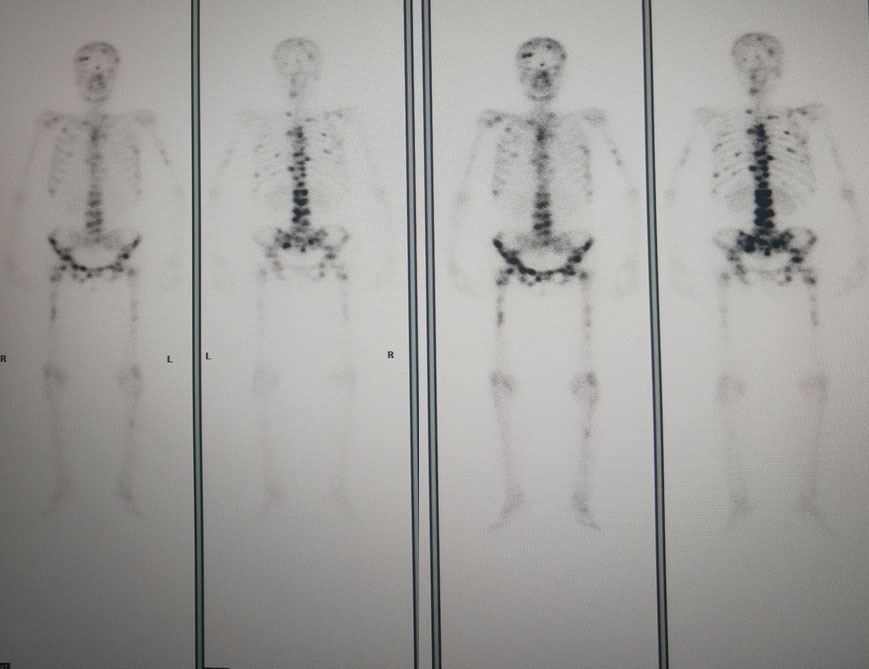

图3.骨扫描

2021年4月7日骨扫描:全身多发骨质代谢异常,考虑多发骨转移。